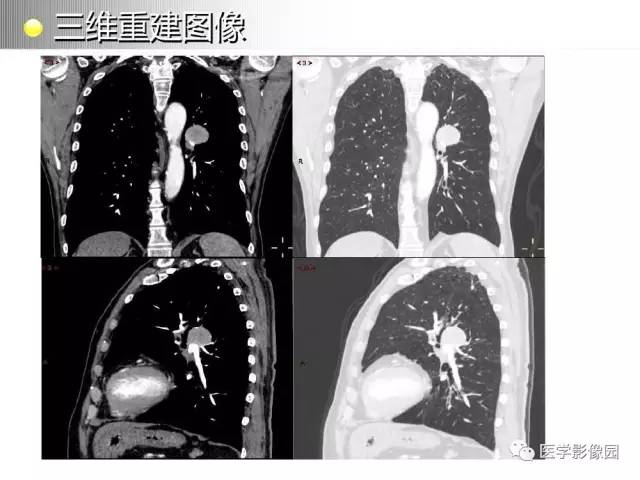

左肺门巨淋巴结增生1例CT影像分析